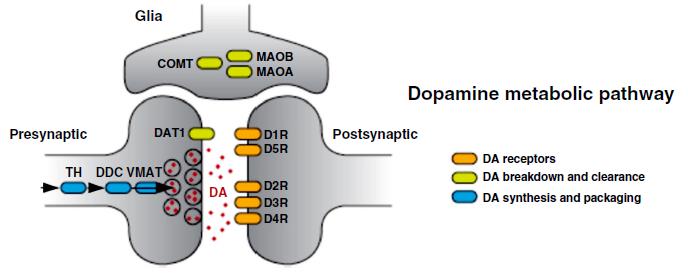

Dopamin, seine D1-, D2-, D3-, D4-, D5-Rezeptoren, beschwichtigend wirkenden D2-,

D3–Autorezeptoren, sein Wiederaufnahme-Transporter DAT und

Abbau-Enzyme COMT und MAO A spielen dabei eine ausschlaggebende Hauptrolle.

untrennbar eng miteinander verbunden. Die folgenden zwei Grafiken zeigen im Überblick neuro- und molekularbiologische Lebensprozesse im Dopaminsystem:

Copyright 2014 by PNAS